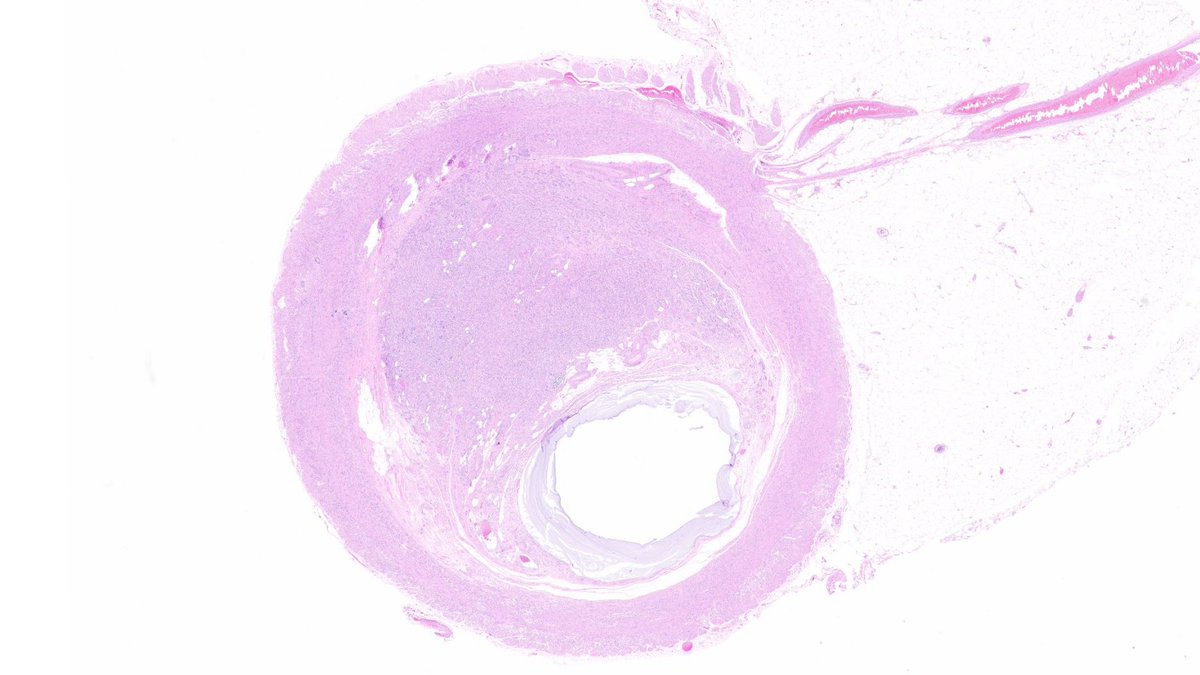

👉71 YO male with urinary bladder mass. [A] is section from the mass. [B] was an incidental finding among the tumor. [C] demonstrates IHC done in that area. PAX8 was negative. What is the diagnosis as seen in A? What is B? Courtesy @annsmiley78 #PathTwitter #GUpath

2

16

39